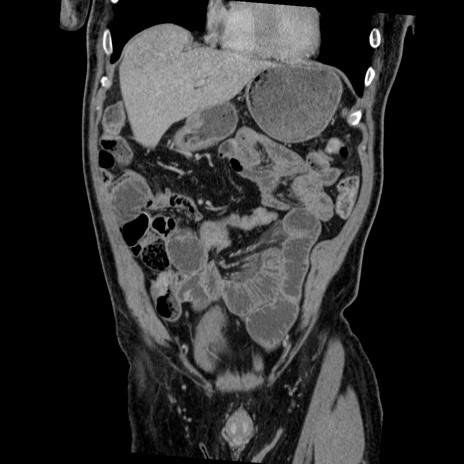

症例22(冠状断像)

【症例】50歳代男性

【主訴】腹痛

【現病歴】AVMからの被殻出血のため回復期リハ病棟入院中。 本日午後3時頃急に下腹部痛が出現した。

【既往歴】AVM、被殻出血、虫垂炎、高血圧

【身体所見】意識晴明、左半身不全麻痺、会話の理解は良好、36.5°C、腹部:膨隆、全体に板状硬、下腹部正中に圧痛点あり、反跳痛-、筋性防御不明、右下腹部にope scar

【データ】WBC 9400、CRP 0.06